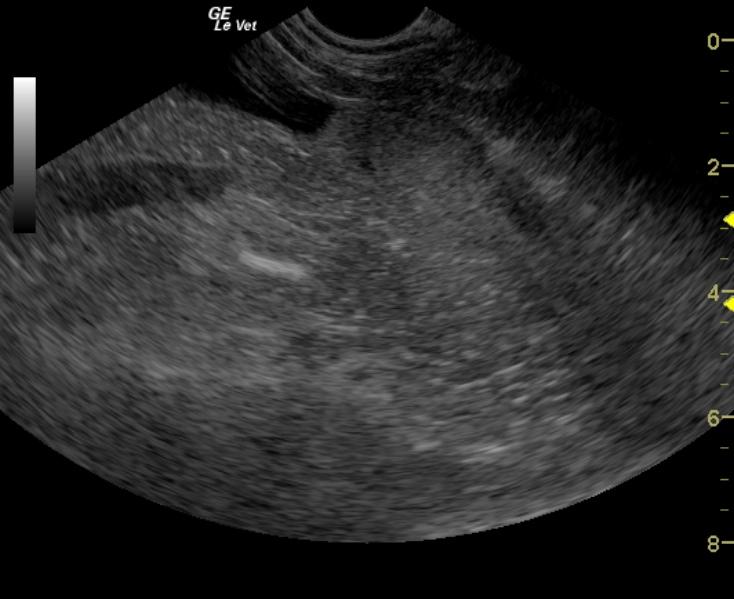

An 11-year-old FS Vizsla was presented for diarrhea, tenesmus, and stranguria for a few months. Rectal exam revealed minor thickening in the urethral region. A Canine diarrhea panel was positive for Clostridium Perfringens Enterotoxin A.